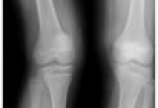

【骨质疏松】洞察秋毫、未雨绸缪——骨质疏松骨折病例分享

病情概述: 女性患者,40岁,体重50Kg。主诉:“右膝关节疼痛伴弹响1年,加重1周。”查体:右膝关节活动尚可,过屈试验(+),过伸试验(+),McMurray试验(+),研磨试验(+),右股四头肌略萎缩。右膝MRI提示:右膝内侧半月板信号不均,增高。病例资料:入… [详情]